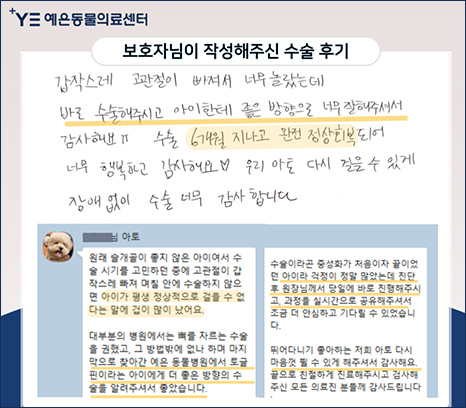

치료 후기 2 토글핀 수술

갑작스레 고관절이 빠져서 너무 놀랐는데 바로 수술해주시고 아이한테 좋은 방향으로 너무 잘해주셔서

감사해요. 수술 6개월 지나고 완전 정상회복되어 너무 행복하고 감사해요. 우리 아토 다시 걸을 수 있게

장애 없이 수술 너무 감사합니다.

원래 슬개골이 좋지 않은 아이여서 수술 시기를 고민하던 중에 고관절이 갑작스레 빠져 며칠 안에

수술하지 않으면 아이가 평생 정사적으로 걸을 수 없다는 말에 겁이 많이 났어요.

대부분의 병원에서는 뼈를 자르는 수술을 권했고, 그 방법밖에 없나 하며 마지막으로 찾아간 예은 동물병원에서

토글핀이라는 아이에게 더 좋은 방향의 수술을 알려주셔서 좋았습니다. 수술이라곤 중성화가 처음이자

끝이었던 아이라 걱정이 정말 많았는데 진단 후 원장님께서 당일에 바로 진행해주시고, 과정을 실시간으로

공유해주셔서 조금 더 안심하고 기다릴 수 있었습니다.

뛰어다니기 좋아하는 저희 아토 다시 마음껏 뛸 수 있게 해주셔서 감사해요. 끝으로 친절하게 진료해주시고

검사해 주신 모든 의료진 분들께 감사드립니다.